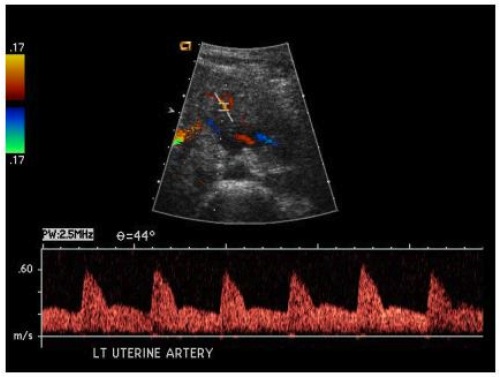

“I disordini ipertensivi – spiega Ferrazzani – si presentano in Italia in circa il 4% delle gravidanze, mentre la preeclampsia nel 1-2%, con una maggior frequenza nella prima gravidanza. La frequenza di preeclampsia nella seconda gravidanza è inferiore all’1% in donne normotese durante la prima gravidanza, mentre la ricorrenza di preeclampsia viene riportata al 15-18%. L’occorrenza di una preeclampsia severa nella precedente gravidanza porta il rischio di ricorrenza al 47%, e, se questa era comparsa nel 2° trimestre, aumenta al 65%”. Si tratta di numeri significativi molto più alti in altri Paesi come gli Stati Uniti (57%), la Svezia o l’Inghilterra. Le cause della preeclampsia non sono note, ma uno dei meccanismi patogenetici della malattia sembra implicare la trombosi della circolazione utero-placentare.

Scopo del trial multicentrico è trovare terapie efficaci per prevenire la preeclampsia o per lo meno limitarne le gravi conseguenze. Il nostro obiettivo è dimostrare l’efficacia del trattamento con eparina frazionata associata ad aspirina a basse dosi in donne con precedenti gravidanze complicate da preeclampsia precoce per migliorare la perfusione placentare e l’outcome neonatale – argomenta Ferrazzani –. Una preeclampsia severa nella prima gravidanza di una donna – continua il ginecologo – può portare il rischio di ricorrenza al 47% nella seconda gravidanza e, se la patologia era comparsa nel 2° trimestre, il rischio aumenta fino al 65%”. Obiettivo del protocollo prospettico randomizzato è quello di verificare se la profilassi antiaggregante e anticoagulante data dall’associazione aspirina a basse dosi ed eparina frazionata può migliorare l’esito di queste gravidanze”.